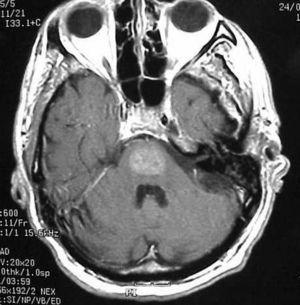

Precisó intubación y ventilación mecánica y se inició tratamiento con dantroleno y diacepam. Al retirar la sedación se apreció monoparesia de extremidad superior izquierda, sin otras alteraciones neurológicas. Una nueva TC cerebral fue normal, sin embargo el cuadro neurológico progresó hasta un síndrome de cautiverio. Se realizó una resonancia magnética nuclear (RMN) (fig. 1) en la que se apreció una mielinolisis central pontina (MCP) con afectación de los ganglios basales.

Figura 1. Corte FSE-T2 sagital con imagen hiperintensa localizada en la protuberancia y ganglios de la base que confirma el diagnóstico de MCP.